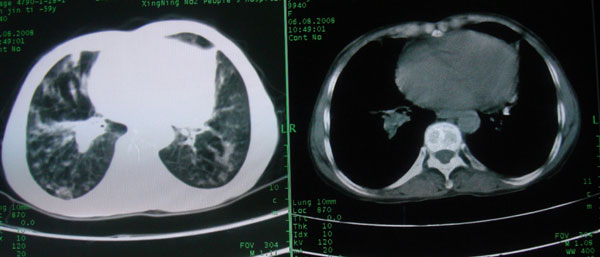

标题: CT15046:F59Y,咳嗽间断咳血丝痰就诊. [打印本页]

标题: CT15046:F59Y,咳嗽间断咳血丝痰就诊.

咳嗽\间断咳血丝痰就诊.

考虑支气管扩张并感染

1慢支伴感染;右下肺周围型肺癌。

1\\慢支并感染

2\\浸润型肺结核

本例应该是“慢性疾病并发多种合并症”即:慢支并感染并支气管扩张征!结合病灶分布 形态分析,不除外合并“继发性肺结核”!